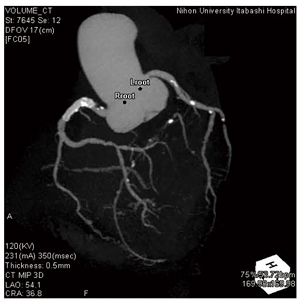

Amazon.com: CT冠動脈造影実践学: 9784498013568: unknown, 冠動脈CTによる狭心症の診断,

冠動脈CTによる狭心症の診断, 沖縄県医師会_沖縄県医師会報(2013年3月号),

桜橋渡辺未来医療病院 MDCT検査予約, 冠動脈CTによる狭心症の診断,

冠動脈CTによる狭心症の診断, 心臓と冠動脈(冠状動脈のCT)の解剖学 : 正常解剖学 | e-Anatomy,